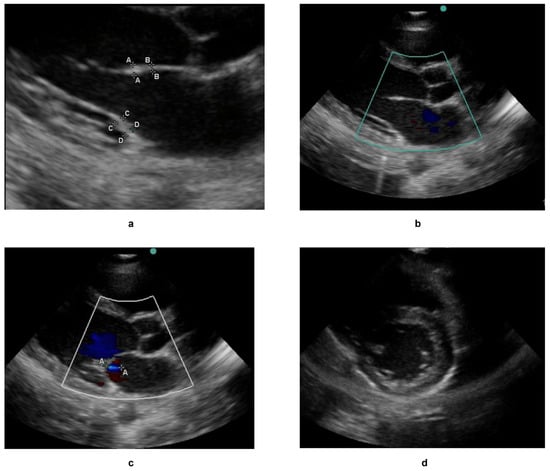

| Filename | Colour | Echo View | Thickness | Condition | Severity | |

|---|---|---|---|---|---|---|

| a | 10.38.47 hrs __[0005903].jpeg | NO COLOUR | Parasternal long axis (PLAX) | Thick | Not applicable | Definite RHD |

| b | 10.39.22 hrs __[0005905].mp4 | COLOUR | Parasternal long axis (PLAX) | Not thick | Aortic valve regurgitation | Borderline RHD |

| c | 10.40.10 hrs __[0005906].jpeg | COLOUR | Parasternal long axis (PLAX) | Not applicable | Mitral valve regurgitation | Normal |

| d | 10.40.15 hrs __[0005907].mp4 | NO COLOUR | Parasternal short axis (PSAX) | Not applicable | Mitral valve prolapse | Not applicable |